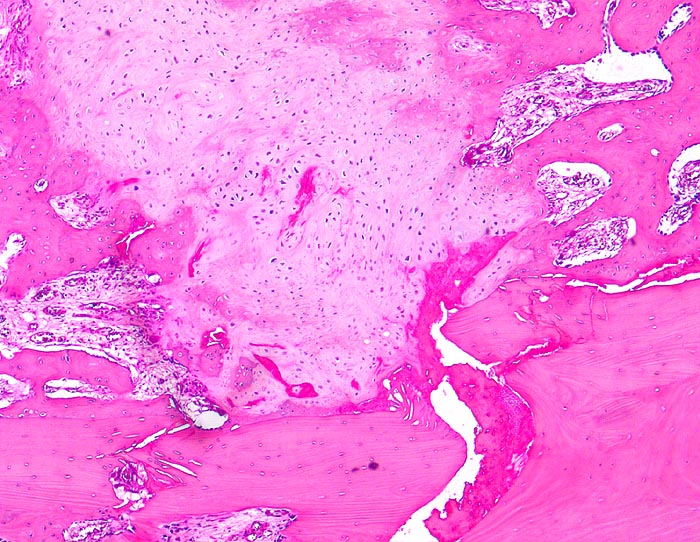

Morphologische Merkmale:

• Verschiebung der Bruchstücke gegeneinander.

• Über dem Frakturspalt senkrecht auf die Frakturlinie ausgerichtete Faserknochenbälkchen mit Osteoblastensaum und ausgedehnte Bezirke von neugebildetem Knorpel.

• Fibrinablagerung und Knorpelneubildung im Frakturspalt.

• Enchondrale Ossifiktation des neugebildeten Knorpels.

• Auch entfernt von der Bruchlinie Neubildung von Knochenbälkchen im Markraum.